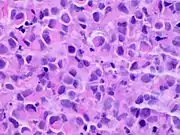

| Pleomorphic | Classical-appearing but with pleomorphic cells. It may include signet-ring cells, or plasmacytoid cells (pictured) which have abundant cytoplasm and eccentric nuclei. |  |

Histopathology of invasive lobular carcinoma (ILC), next to lobular carcinoma in situ (LCIS).jpg.webp) Invasive lobular carcinoma demonstrating a predominantly lobular growth pattern